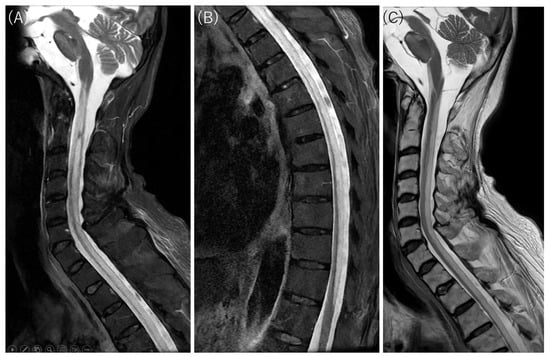

Thoracolumbar STIR FSE MRI findings (axial section). Corresponding to the hyperintensities seen on DWI, high signal intensities are observed within the spinal cord extending down to the lumbar level on STIR-FSE images. In the axial sections, diffuse hyperintensities are noted in the anterior, lateral, and posterior columns. Conversely, the areas with preserved signal intensity are consistent with the spinal gray matter, which appears markedly atrophic. This tract-predominant distribution is a key imaging signature that distinguishes this case from typical spinal cord infarction (SCI), which follows specific arterial territories (anterior or posterior spinal arteries). While venous infarction similarly lacks arterial territory adherence, it is excluded here due to its rarity and the absence of predisposing vascular malformations. Methotrexate (MTX) neurotoxicity is a potential synergistic factor in this case. Although typically associated with intrathecal administration, oral MTX used for the patient’s rheumatoid arthritis can induce white matter vacuolar degeneration [8,9,10]. The observed tract-predominant distribution—specifically involving the posterior and lateral columns—aligns with the known patterns of MTX-induced cord injury, albeit rarely manifesting as such longitudinally extensive involvement from oral dosing. Suspected late-onset ornithine transcarbamylase (OTC) deficiency is supported by hallmark biomarkers, including hyperammonemia, urinary orotic acid, and low citrulline [11,12], though definitive genetic or enzymatic confirmation was not performed. Mechanistically, hyperammonemia-induced glutamine accumulation leads to astrocyte swelling and cytotoxic edema [11,12,13], potentially explaining the diffuse, tract-predominant diffusion restriction observed from the brainstem to the spinal cord. Folate deficiency (potentially due to MTX’s side effect) and hypocupremia (34 μg/dL) might act as synergistic factors in this LESCL, as copper is essential for mitochondrial electron transport and myelin maintenance [14,15,16,17]. Resulting enzymatic dysfunction typically manifests as symmetric T2 hyperintensities in the dorsal and lateral columns [14,15,16,17]. Collectively, the imaging and biochemical profile suggests a catastrophic metabolic breakdown of the spinal white matter architecture driven by the combined effects of suspected late-onset OTC deficiency, hypocupremia, and MTX-induced neurotoxicity. When neuroimaging patterns mismatch recognized vascular or inflammatory territories, complex metabolic and toxic etiologies must be prioritized in the differential diagnosis of LESCL. L: left; R: right.